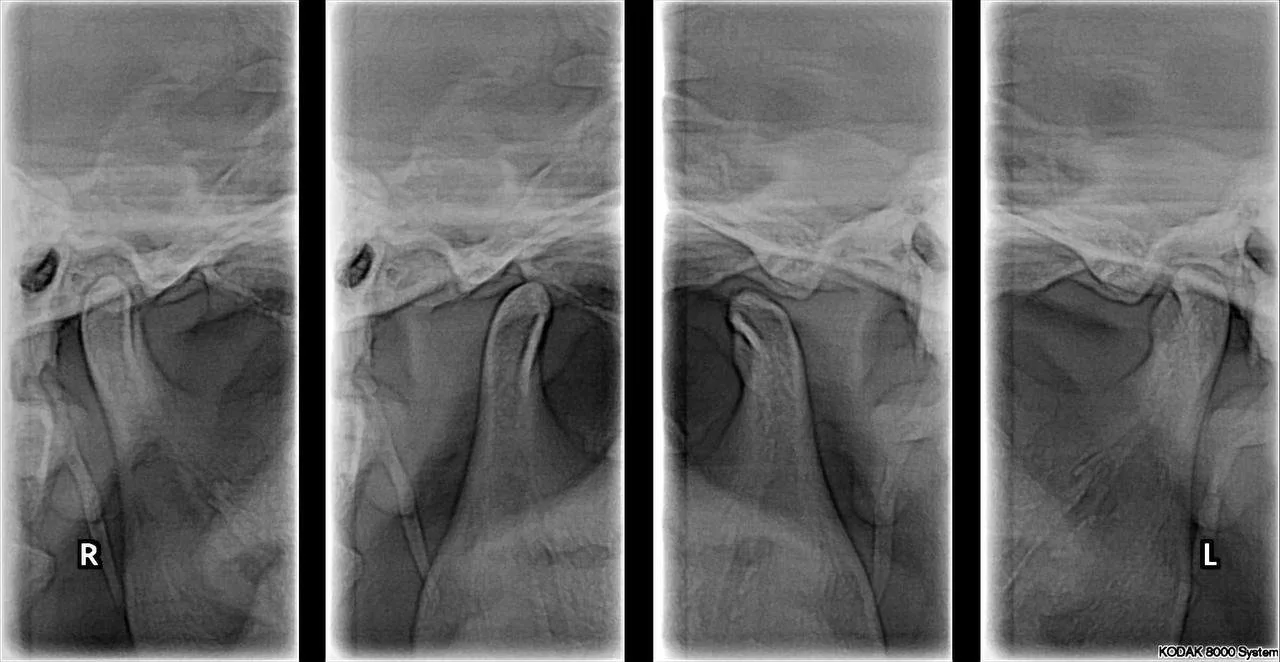

Radiografía de ATM (Boca abierta y boca cerrada)

La radiografía de la articulación temporomandibular (ATM) permite evaluar la posición, morfología y relación de los cóndilos mandibulares.

Es un estudio de apoyo fundamental en pacientes con dolor articular, limitación de apertura o trastornos temporomandibulares.